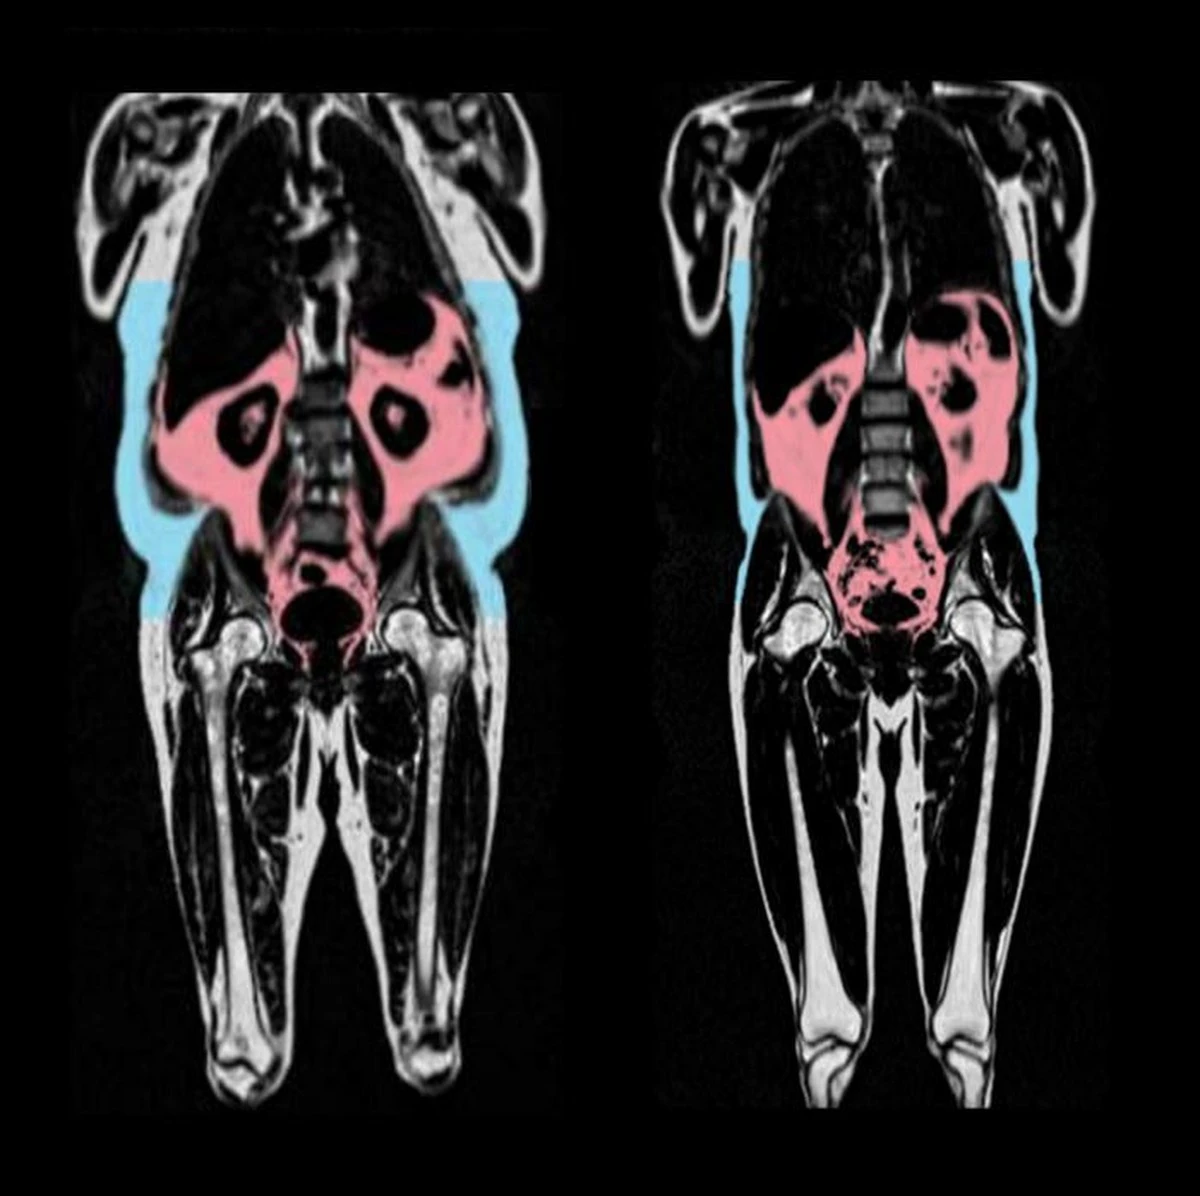

Un estudio realizado en el Reino Unido analizó datos de casi 26.000 participantes que se sometieron a resonancias magnéticas (RM) completas. Los científicos utilizaron una técnica especializada, mapas de fracción de grasa por densidad de protones, que permite medir con precisión la cantidad de grasa en cada órgano.

Paralelamente, se realizaron resonancias magnéticas cerebrales cuyos datos fueron analizados por inteligencia artificial entrenada para determinar la "edad biológica" del cerebro. Así, los investigadores pudieron comparar cómo se ve el cerebro de una persona y cuántos "años" tiene realmente, según los cambios estructurales.

Los resultados fueron contundentes: las personas con mayor cantidad de grasa interna presentaban un cerebro "más viejo" y una mayor pérdida de sustancia gris.

Dos perfiles de riesgo peligrosos

Los investigadores identificaron dos patrones de distribución de grasa que están más fuertemente asociados con el envejecimiento acelerado del cerebro:

- El perfil predominante de páncreas: En estas personas, la concentración de grasa en el páncreas rondaba el 30%, significativamente más alta que en otros grupos. Esto se correlacionaba fuertemente con un cerebro de apariencia más envejecida y un deterioro de las funciones cognitivas.

- El modelo "delgado-graso": Estos individuos tenían solo un ligero aumento en su índice de masa corporal, pero una acumulación considerable de grasa interna combinada con una disminución de la masa muscular. Aunque externamente parecían tener un peso normal, sus cerebros envejecían más rápido.